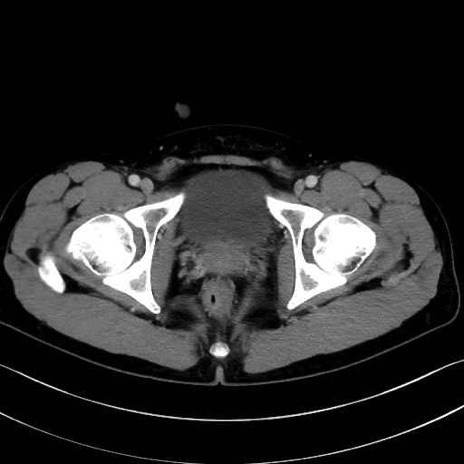

恥骨筋(pubic muscle) のCT画像の解剖

恥骨筋 (Pectineus)

長内転筋 (Adductor longus)

短内転筋 (Adductor brevis)